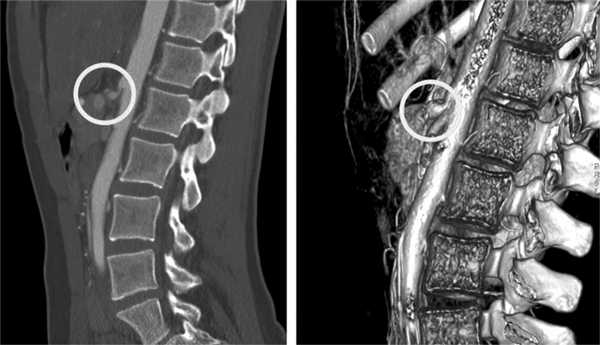

Во всех наблюдениях выполнена МСКТ брюшной полости с внутривенным усилением («Визипак»), при которой был подтвержден диагноз КСЧС (рис. 1). Наиболее показательна информация, полученная в сагиттальных срезах.

Рис. 1. Мультиспиральная компьютерная томограмма с внутривенным усилением и 3D-реконструкция при КСЧС. Маркером отмечен участок сужения чревного ствола с зоной постстенотического расширения.

При анализе данных МСКТ изучали анатомию ЧС и его основных ветвей, особенности их строения, определяли зону локального сужения и постстенотического расширения. Полученные данные уточняли при 3D-реконструкции.